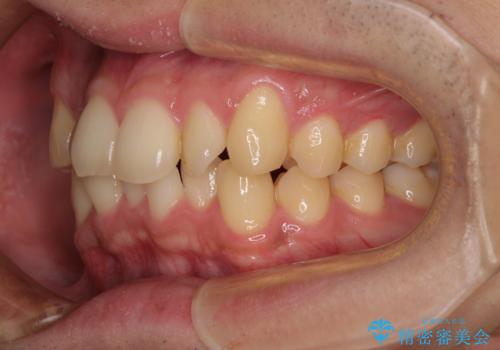

- 上下前歯の捻れやデコボコを気にして来院された患者様です。

マウスピース矯正でもワイヤー矯正でも対応可能でしたが、極力楽をして治したいとのことでワイヤー装置にて治療をおこなうこととしました。

口元はそれほど突出しておらず、患者様自身も気にしていらっしゃいませんでしたが、前歯の捻れやデコボコを解消すると、前方に拡大され、治療後に出っ歯仕上がりとなるリスクがあったため、補助装置により上顎臼歯を後方移動していくこととしました。